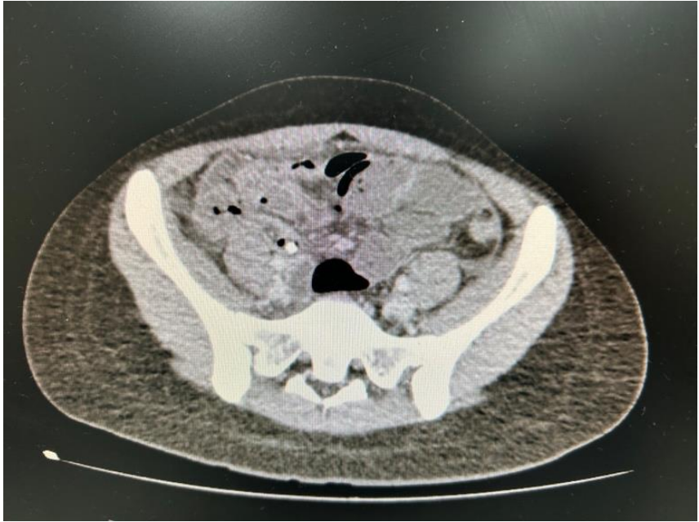

Paciente feminina, 18 anos, procurou atendimento em UPA com queixa de dor abdominal em baixo ventre há 2 dias e recebeu antibioticoterapia com ciprofloxacina para infecção do trato urinário. Sem melhora dos sintomas após 3 dias de tratamento, procurou um hospital de referência apresentando piora da dor abdominal, além de náuseas e vômitos. Ao exame físico, a paciente estava descorada (1+/4+), desidratada (2+/4+), afebril ao toque, com abdome tenso e doloroso à palpação em flanco e fossa ilíaca direita, com sinal de Giordano negativo.

Exames laboratoriais: Hemoglobina: 12,6 g/dL, Leucócitos: 16.260/mm³, Plaquetas: 260.000/mm³, Creatinina: 1,01 mg/dL, Ureia: 21,8 mg/dL, INR: 1,15, PCR: 23,9 mg/L (VR<1,0).

Realizou tomografia computadorizada de abdome com contraste venoso para investigação que apresentou o seguinte achado.

Dentre os diagnósticos diferenciais para esse caso, qual dos seguintes é o mais provável?